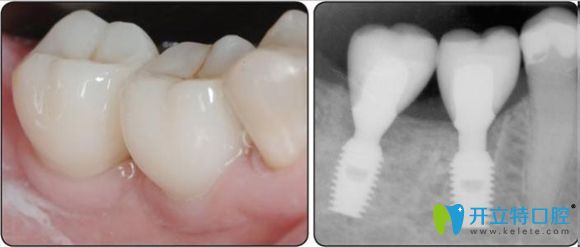

登特斯種植體與基臺(tái)間是漸細(xì)的錐形六角鏈接封閉式結(jié)構(gòu),保證了與外界的充分隔絕。

植體螺紋高度的增加提高了初期穩(wěn)定性,同步雙螺紋可縮短種植體植入時(shí)間,螺紋間距的加寬有助于早期骨整合。生物性連接可將負(fù)荷均勻的分散在種植體上,有效地減少骨吸收。

韓國登特斯種植牙示意圖